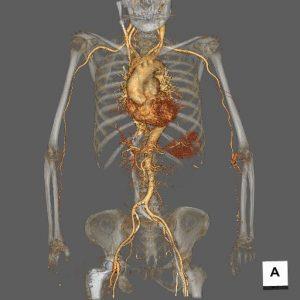

血管撮影検査

腕や足の比較的太い血管からカテーテルと呼ばれる細い管を入れ、心臓や脳、腹部の血管など選択的に挿入し、その先から造影剤を注入し、造影された血管の走行状態、病変まで撮影、治療を行います。

心臓用、頭部用、腹部用(+IVRCT)、ハイブリッド血管撮影装置の4台の装置が稼働しており、緊急検査・治療にも対応しています。